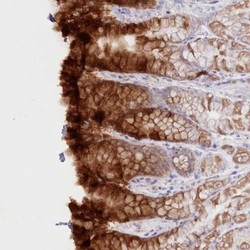

- Main image

- Experimental details

- Immunohistochemistry: PSAPL1 Antibody [NBP2-32635] - Staining of human stomach, lower shows strong cytoplasmic positivity in glandular cells.